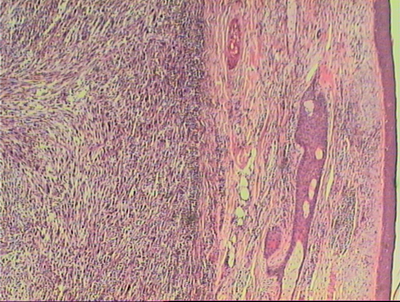

AbstractIn the following case report we describe a 66 year-old man who was presented with a squamous cell carcinoma (epithelial tumour) on the skull which grew on the scar of a previously surgically excised sarcoma (mesenchymal tumour). This is the first description of such a coincidence, which may be due to the development of a mutated stem cell colony, which differentiated in tumour cells of several lineages. Case reportThe 66 year-old patient presented to our Departments with a 3-month history of a 0.5 x 1 cm large, erythematous, ulcerated skin lesion over the medial side of a surgical scar on the left parietal side of the scalp (as shown in figure 1a). The scar (as shown in figure 1b) was due to surgical excision of a sarcoma (G2) 5 years ago [1]. At that time the dermatological examination of the patient had detected a painless solitary 3 x 5 cm large, erythematous swelling (as shown in figure 2a) and the histopathological examination (as shown in figure 2b) had detected pleomorphic mesenchymal cellular regeneration in the subcutaneous tissue with a limited nodular process. A focal fibrotic false capsule had been seen. The tissue had shown myxoid infiltration. An immune histochemical staining had revealed negative results for CD34, S100, actin, desmin and pancytokeratin staining, while labeling with the Ki67 antigen had detected a proliferation rate of 80%. The skull computer tomography prior to surgical excision of the tumour has shown a localized space-occupying lesion in the soft tissue without intracranial metastasis. The chest computer tomography did not reveal any pathological signs. The regular oncological follow-up of the patient every 6 months has detected two basal cell carcinomas over the left side of the back and the right lower limb after 2 years, which were treated surgically with elliptical excisions. The current lesion on the skull was also detected at the regular follow-up and was surgically excised. The histological examination showed orthohyperkeratosis, epidermal hyperplasia with disturbance in the cell arrangement of the lower epidermal layers associated with cellular and nuclear polymorphism. In addition, proliferation of atypical epithelial growth in the upper dermis was seen (as shown in figure 1a). The diagnosis of squamous cell carcinoma was concluded with a total depth of 0.7 mm. There was no evidence of sarcoma recurrence. The regional lymph nodes and the chest were free of lesions in imaging examinations. DiscussionSoft tissue sarcomas account for 1% of all malignancies. Approximately 60% of soft-tissue sarcomas arise in the extremities. The lower extremities are three times more often involved than the upper extremities. Further sites involved are the trunk (19%), the retroperitoneum (15%), and the head and neck (9%) [2]. Approximately 80% of head and neck sarcomas occur in adults, whereas the most common subtypes are osteosarcoma, angiosarcoma, malignant fibrous histiocytoma, and fibrosarcoma, and 10-20% occur in children, the most common subtype being rhabdomyosarcoma [3]. On the other hand, squamous cell carcinoma is the second most common malignancy of the skin after basal cell carcinoma and the skin is the most common site for squamous cell carcinoma [4]. It accounts for 20% of cutaneous malignancies and 80-90% of all head and neck cancers [5]. Sun exposure is a major risk factor for epithelial tumours, while sarcoma growth does not seem to be related to sun exposure. In our patient, skin tumours of different lineage, namely squamous cell carcinoma of epithelial (ectodermal) and sarcoma of mesenchymal (endodermal) origin, occurred at the same skin region in a period of 5 years the former developed over the scar of the latter: Such a coincidence has not been reported before. Since these lesions were the only tumors detected in this patient, a mutated stem cell colony, which is able to differentiate in cells of several lineages, could be speculated [6]. References1. WHO classification of soft tissue tumours. 2006; 10-17.2. Potter BO and Sturgis EM. Sarcoma of head and neck. Surg Oncol Clin N Am 12:379-417, 2003. 3. Sidappa KT and Krishnamurthy A. Adult soft-tissue sarcomas of the head and neck. Indian J Dermatol 48:284-288, 2011. 4. Papadopoulos O, Frantzoglou M, Chrisostomidis C, Konofaos P, Frangoulis M and Barlas G. Neglected squamous cell carcinoma of the frontal area: a clinical report. J Craniofac Surgery 17:1015-1020, 2006. 5. Hiu CS, Lin CY, Kuo TT, Kuan YZ, Chen MJ, Ho HC, Yang LC, Chen CH, Shih IH, Hong HS and Chuang YH. Malignant cutaneous tumors of the scalp: a study of demographic characteristics and histologic distributions of 398 Taiwanese patients. J Am Acad Dermatol 56:448-452, 2007. 6. Zouboulis CC, Adjaye J, Akamatsu H, Moe-Behrens G and Niemann K. Human skin stem cells and the ageing process. Exp Gerontol 43:986-997, 2008. © 2012 Egyptian Dermatology Online Journal |